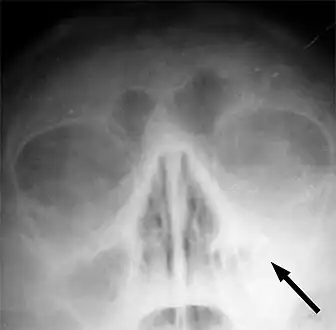

CT of chronic sinusitis

CT scan of chronic sinusitis, showing a filled right maxillary sinus with sclerotic thickened bone